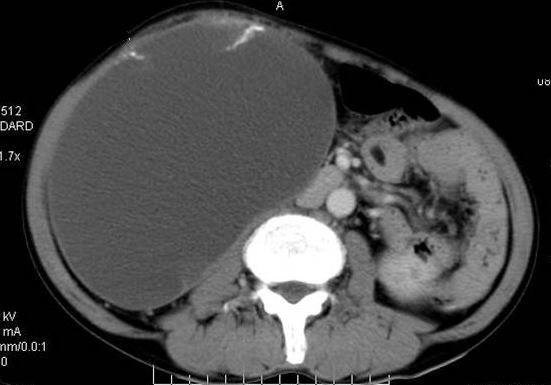

男性 60岁,腹部肿块4年余,肿块逐渐增大,活动性差,无血尿。

平扫